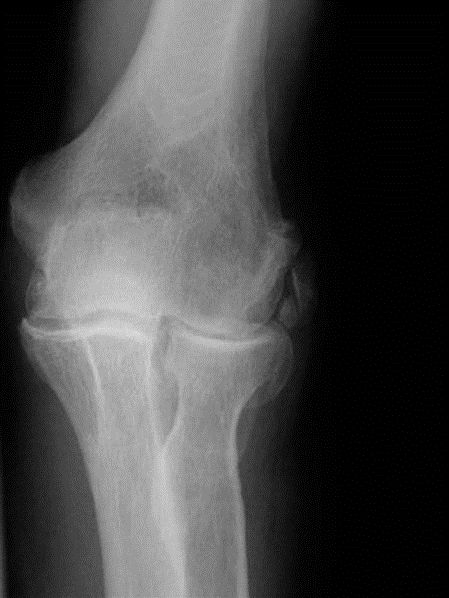

Question 1

A 55-year-old male former professional baseball pitcher presents with 3 years of progressive right elbow pain, stiffness, and occasional locking. His pain is worse with activity and he notes difficulty with full extension and flexion. Physical examination reveals a flexion contracture of 20 degrees and further flexion to 120 degrees, with crepitus throughout the range of motion. Ulnar nerve symptoms are intermittently present. Radiographs show extensive osteophyte formation on the olecranon and coronoid fossae, along with capitellar and trochlear spurring. There is also evidence of loose bodies. What is the most appropriate initial surgical management for this patient?

This patient presents with classic symptoms and radiographic findings of primary elbow osteoarthritis, likely exacerbated by his history as a professional pitcher. Given the progressive pain, stiffness, mechanical symptoms (locking), and specific radiographic findings of osteophytes and loose bodies, open debridement with osteophyte excision and loose body removal is the most appropriate initial surgical intervention. This procedure aims to restore motion, reduce pain, and address mechanical impingement. Total elbow arthroplasty (TEA) is typically reserved for severe, end-stage osteoarthritis, particularly in older, low-demand patients, and is not indicated as an initial approach for a patient of this age and activity level unless conservative measures and debridement have failed. Ulnar nerve transposition may be part of the procedure if persistent ulnar neuropathy is present after debridement, but it is not the primary intervention for the OA itself. Radial head excision is indicated for radiocapitellar arthritis or specific fracture patterns, not the comprehensive OA described. Distraction arthroplasty is a less common salvage procedure for severe cases, also not initial management.

Which of the following radiographic findings is typically considered the earliest sign of primary elbow osteoarthritis?

Explanation

What is the most common radiographic finding in early primary elbow osteoarthritis?